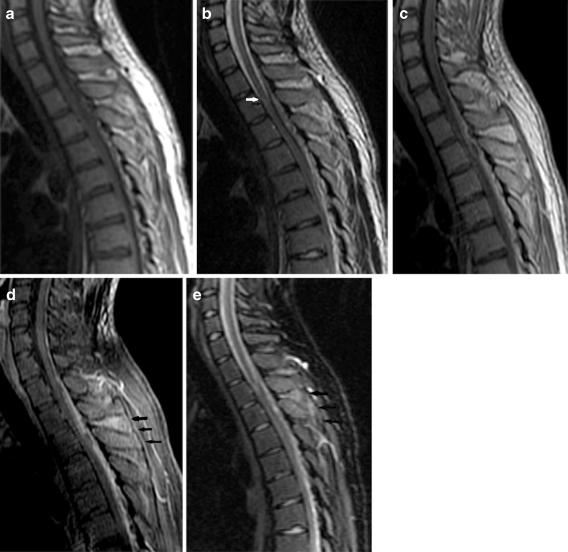

A posterior epidural mass causing paraparesis in a 20-year-old healthy individual.

We present a case of a posterior epidural abscess at the thoracic vertebral level causing paraparesia in a young, healthy individual with no otherwise predisposing factors, with normal laboratory findings, as diagnosed using fat-suppressed MR imaging. Spinal epidural abscess is a rare condition, encountered mostly in the midthoracic or lower lumbar vertebral levels of elderly patients, that has a high mortality and morbidity (18-31%) when diagnosis and treatment is delayed. It is rarely spontaneous and is usually accompanied by spinal osteomyelitis. Diagnosis is rather easy in cases of vertebral osteomyelitis or when classical clinical, laboratory and imaging findings are present. However, cases of spontaneous development, with no predisposing factors, and lack of abscess suggesting clinical and laboratory findings may be a diagnostic challenge. In such cases, other posterior epidural masses such as schwannoma, neurofibroma, meningioma and hematoma should be considered in the differential diagnosis. Both the clinician and the radiology physician should have a high suspicion of epidural abscesses, because their early diagnosis and treatment is important. In addition to routine MR images, fat-suppressed MR images prove helpful in the diagnosis of spontaneous epidural abscesses by showing the inflammatory changes in the paraspinal area.